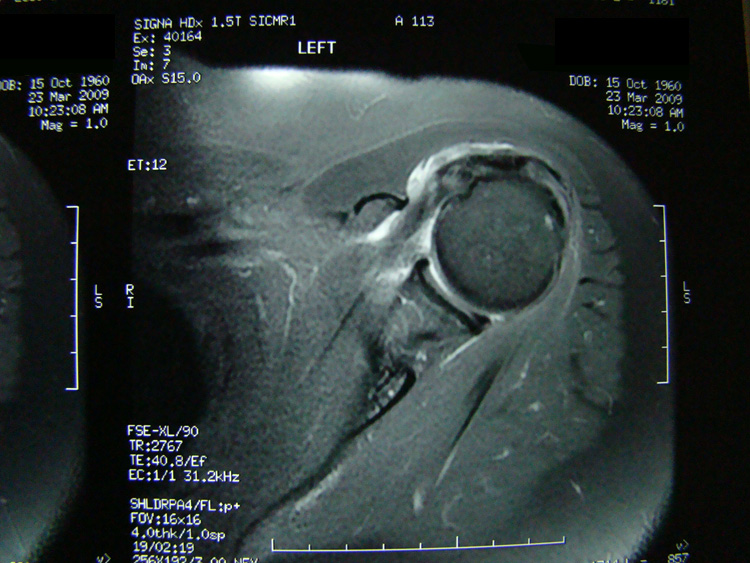

This patient presented with shoulder pain that interfered with work and exercise. The visible fluid-filled cysts on the “Before" MRIs are from chronically injured rotator cuff tendon roots.

The patient underwent treatments of a highly specialized fine-needling technique pioneered by Dr. Tallman.The follow-up MRI was done 2 months after his 6th treatment. He was released with a pain-free, full range of motion with unrestricted activities.